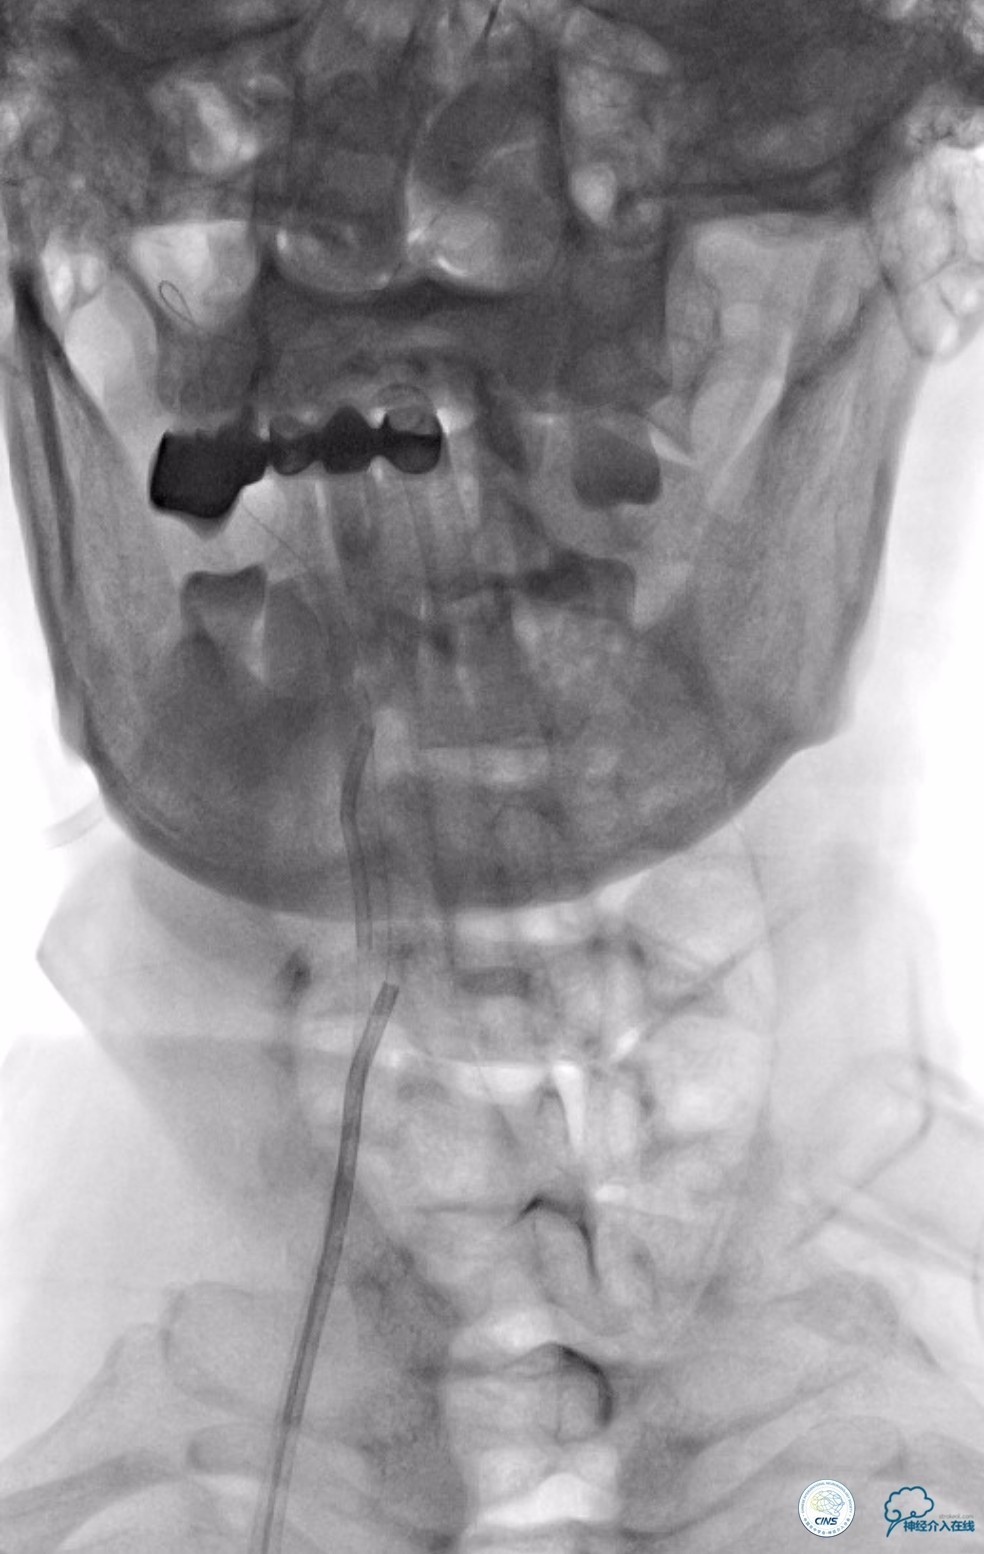

撤出Echelon-10微导管及5F导引导管。沿6F导引导管送入Select Plus微导管至基底动脉远端。经微导管送入Enterprise 4.5mm×28mm至右椎动脉V4段,两个支架重叠约2-3mm,完全覆盖右椎动脉V4段夹层(图13)。

图13

动脉粥样硬化狭窄合并动脉瘤的处理,因治疗狭窄和栓塞动脉瘤的两套系统常需要并列使用,事先要考虑所用导引导管是否能完全容纳两套系统,如本例8F导引导管到位困难,故只能改用两套系统完成治疗(图14)。

图14